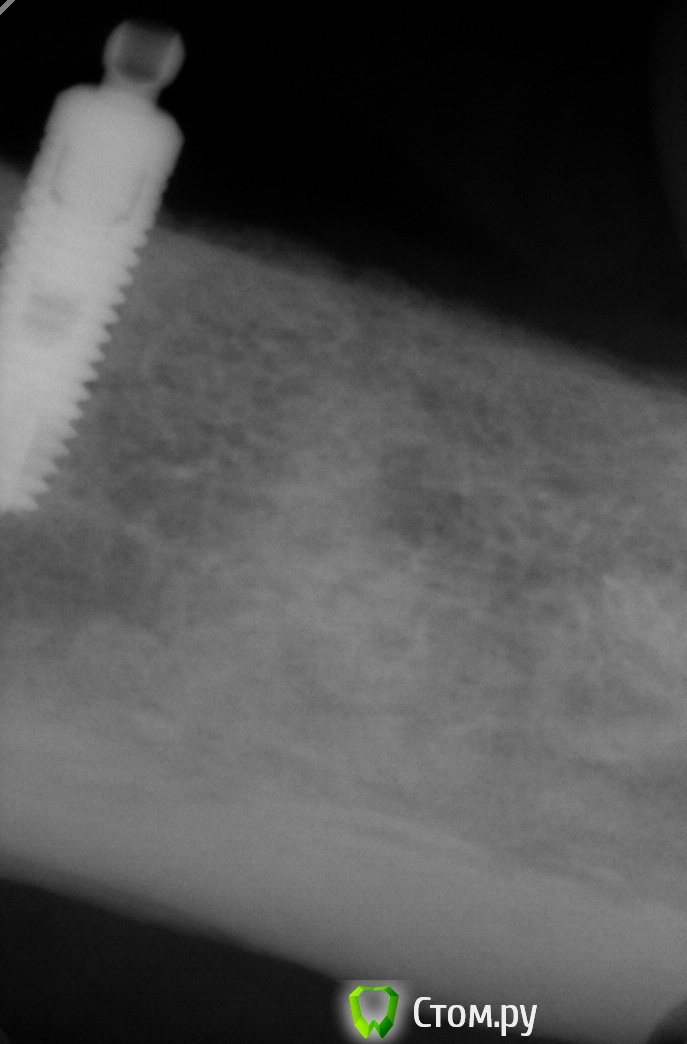

Pro100Andre Опубликовано 31 октября, 2014 Поделиться Опубликовано 31 октября, 2014 сегодня пришла пациентка с ПСПП фиксация на шаровидных абатментах, матрицы значительно изношены, на прицельном два разных имплантата помогите определить что за система, знаю есть сайт со снимками но немогу его найти... Ссылка на комментарий

Acidrocker Опубликовано 31 октября, 2014 Поделиться Опубликовано 31 октября, 2014 но как правило не находил там нужный( снимок еще не очень показательный. похоже на альфабио атид Ссылка на комментарий

ILGAMSA Опубликовано 31 октября, 2014 Поделиться Опубликовано 31 октября, 2014 астра это 3.5/4.0 1 Ссылка на комментарий

faity Опубликовано 3 ноября, 2014 Поделиться Опубликовано 3 ноября, 2014 астра, только как она блин так оголилась на всю микрорезьбу.... Ссылка на комментарий

andr99 Опубликовано 3 ноября, 2014 Поделиться Опубликовано 3 ноября, 2014 астра, только как она блин так оголилась на всю микрорезьбу....думаю, глядя на уровень кости по всему профилю гребня в этой области, изначально была установлена супра. Ссылка на комментарий